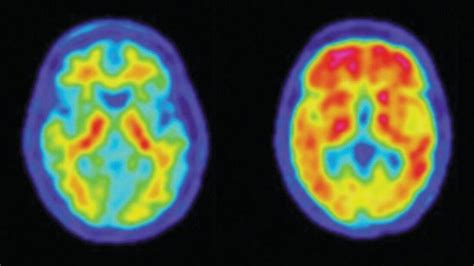

So, what is a PET scan, anyway? At its core, a PET scan is a type of medical imaging that uses a small amount of radioactive material, called a radiotracer , to show how your organs and tissues are functioning. Unlike X-rays or CT scans that show the structure of your body, PET scans reveal metabolic activity. Pretty neat, right? The radiotracer is usually injected into a vein, swallowed, or inhaled, and it travels through your body. The most common radiotracer used is a form of glucose (sugar) because cancer cells, for example, tend to use more sugar than normal cells. As this radiotracer collects in certain areas, it emits tiny particles called positrons. When these positrons collide with electrons in your body, they produce gamma rays. The PET scanner detects these gamma rays, and a computer uses this information to create detailed 3D images. These images highlight areas where the radiotracer has accumulated, indicating higher metabolic activity. This allows doctors to see things like blood flow, oxygen use, and sugar metabolism – essentially, how your body is working at a cellular level. It’s like getting a glimpse into the engine room of your body, showing us where the action is happening, not just the structure. This functional information is incredibly valuable for diagnosing diseases very early on, sometimes even before structural changes become apparent. The process itself is usually painless, although you’ll need to lie still for a while. We’ll get into the nitty-gritty of what to expect later, but for now, just remember that PET scans are all about looking at function rather than just form .

Now, you might be wondering, “Why is looking at function so important?” Great question, guys! The real power of PET scans lies in their ability to detect diseases at their earliest stages and to provide crucial information for treatment planning and monitoring. For instance, in oncology (cancer care), PET scans are a game-changer. They can help doctors differentiate between cancerous and non-cancerous tumors, detect if cancer has spread to other parts of the body (metastasis), and assess how well a tumor is responding to treatment. Imagine a patient undergoing chemotherapy. A PET scan can show if the cancer is shrinking or becoming less active before structural changes are visible on other imaging tests. This allows for timely adjustments to the treatment plan if it’s not working effectively. Beyond cancer, PET scans are invaluable for diagnosing and managing neurological disorders. They can help identify changes in brain activity associated with Alzheimer’s disease, Parkinson’s disease, epilepsy, and other brain conditions. For example, in Alzheimer’s, PET scans can reveal patterns of reduced metabolic activity in specific brain regions, offering a clearer picture of the disease’s progression. They’re also used in cardiology to assess blood flow to the heart muscle, helping to diagnose coronary artery disease and determine the extent of damage after a heart attack. In essence, PET scans provide a unique window into the body’s internal processes, offering insights that other imaging techniques simply can’t. This detailed functional information empowers healthcare professionals to make more accurate diagnoses, personalize treatments, and ultimately improve patient outcomes. It’s this ability to see the unseen, the subtle changes happening at a cellular level, that makes PET scans an indispensable tool in modern medicine. They are truly at the forefront of diagnostic imaging, pushing the boundaries of what we can see and understand about human health.

Guys, one of the coolest things about PET scans is how versatile they are, and a big part of that versatility comes from the different types of radiotracers that can be used. While we often hear about the glucose-based tracer (FDG - fluorodeoxyglucose), it’s definitely not the only game in town! The choice of radiotracer depends entirely on what doctors are trying to see or study within the body. For diagnosing and monitoring cancer, FDG is the superstar because, as we mentioned, cancer cells often gobble up more glucose than healthy cells, making tumors light up on the scan. But what about other conditions? Well, for brain imaging, especially for conditions like Alzheimer’s disease, other tracers are used. For instance, some tracers can bind to amyloid plaques, which are abnormal protein deposits in the brain associated with Alzheimer’s. Another tracer can highlight tau tangles, another hallmark of the disease. These specialized tracers allow neurologists to visualize the specific pathological changes occurring in the brain, aiding in earlier and more accurate diagnoses. In cardiology, tracers that assess blood flow or the viability of heart muscle are employed. They can help pinpoint areas of the heart that aren’t receiving enough blood or areas that have been damaged by a heart attack but might still be salvageable with treatment. There are even tracers being developed and used to detect specific types of receptors or enzymes within the body, opening up possibilities for personalized medicine. For example, a radiotracer might be designed to bind to a specific protein that is overexpressed on certain types of cancer cells. By using this targeted tracer, doctors can get a clearer picture of the extent of the disease and potentially even guide targeted therapy. The development of new radiotracers is a rapidly evolving field, constantly expanding the diagnostic and therapeutic potential of PET imaging. It’s this ability to tailor the tracer to the specific medical question that makes PET scans such a powerful and adaptable diagnostic tool. It’s not a one-size-fits-all approach; it’s a sophisticated system that can be fine-tuned for a vast array of medical investigations, offering precise insights into complex biological processes.